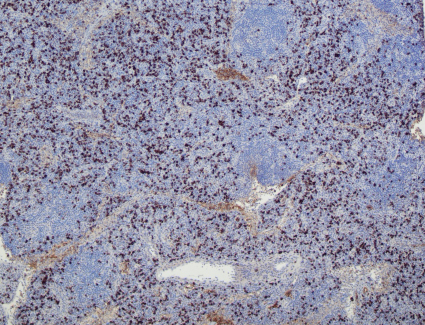

Kappa

Lambda

IgG4

HHV8

The low power view shows lymph node tissue with abnormal follicles, including partial hyalinization, regression of germinal centers, and concentric mantle zone lymphocytes showing "onion skinning" appearance. Several follicles show prominent penetrating venules. No Hodgkin-Reed-Sternberg cells or LP cells were identified.

Immunohistochemical staining shows a polytypic plasmacytosis with no increase in IgG4+ plasma cells. HHV8 staining is negative.